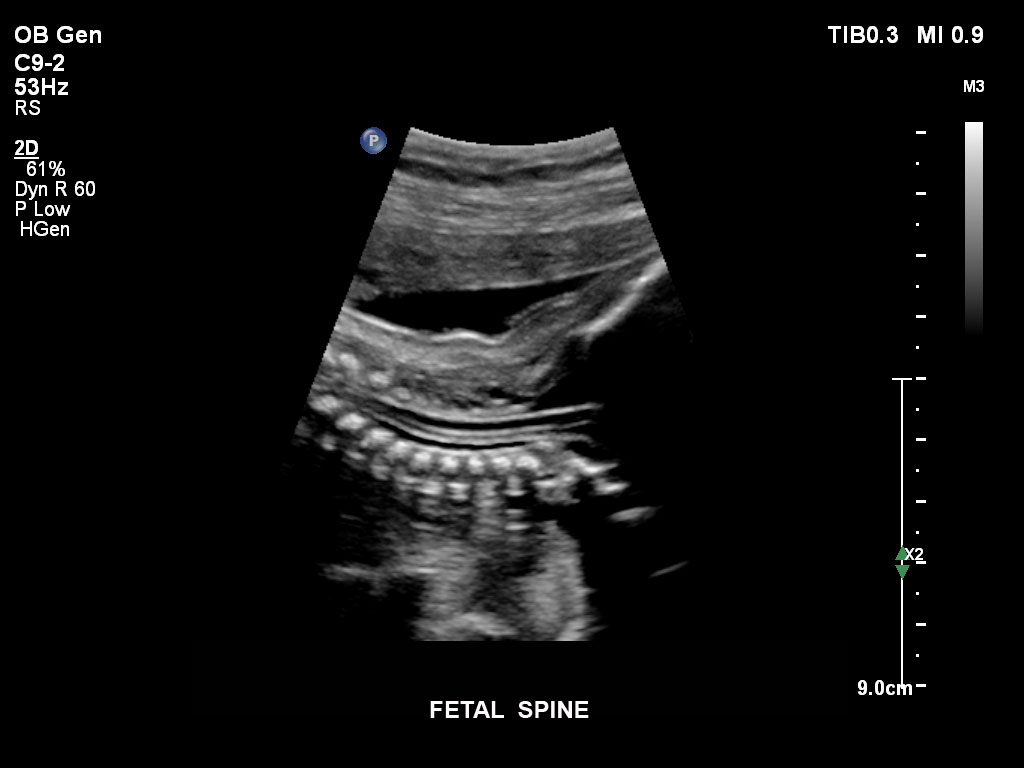

• C9-2 PureWave-Breitband-Convex-Schallkopf für Hochfrequenz-Bildgebung in der Gynäkologie und der Geburtshilfe, insbesondere für die Untersuchung im Hinblick auf mögliche Anomalien im ersten Schwangerschaftstrimester